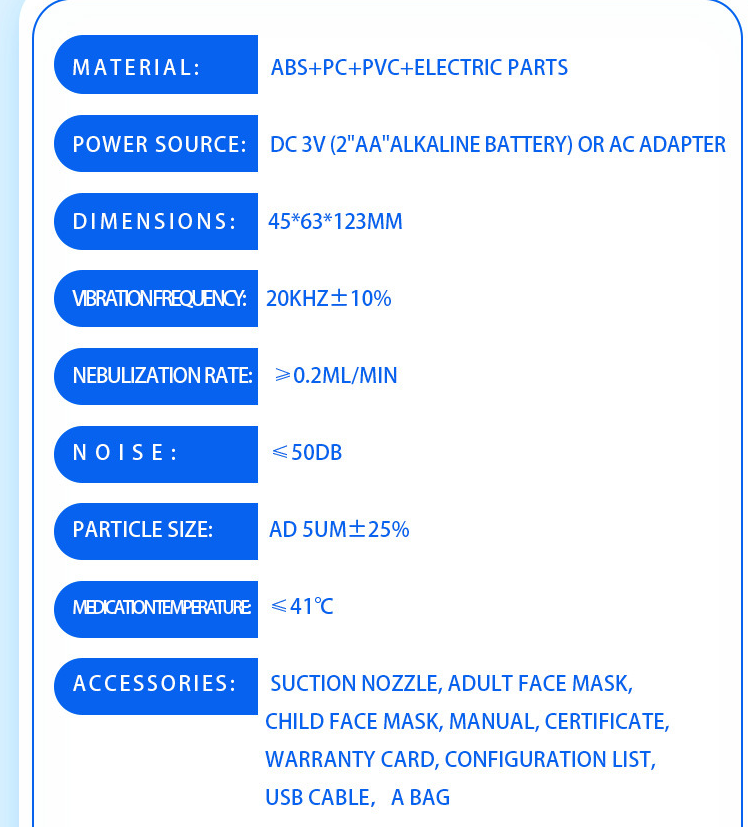

Experience the convenience of the Portable Micro Net Atomizer, your go-to solution for on-the-go inhalation therapy. This handheld nebulizer is designed for both ease of use and effective medication delivery, making it perfect for those who need respiratory relief anytime, anywhere.

Featuring a sleek design and lightweight construction, this atomizer is powered by either dry or lithium batteries, ensuring you have the flexibility to use it whenever you need. Its compact size makes it easy to carry in your bag or pocket, allowing you to maintain your health regime without interruption.

With its advanced micro-net technology, the nebulizer delivers medication in fine mist form, ensuring maximum absorption and effectiveness. Whether you are dealing with allergies, asthma, or other respiratory issues, this device will provide you with the relief you need.

Introducing the Outdoor Portable Nebulizer, your essential companion for quick and effective asthma relief! Designed for both kids and adults, this silent mesh mini inhaler is perfect for on-the-go use, ensuring that you can manage breathing difficulties anytime, anywhere.

This sleek and compact nebulizer comes equipped with everything you need for a seamless experience:

Whether you're at home, work, or outdoors, the Outdoor Portable Nebulizer ensures you have access to essential respiratory care. Its compact design and lightweight build make it easy to carry in your bag.